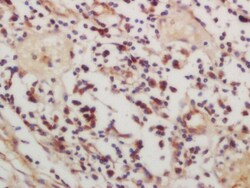

- Main image

- Experimental details

- Formalin-fixed and paraffin embedded human lung carcinoma labeled with Rabbit Anti-CSK (Ser364) Polyclonal Antibody, Unconjugated (bs-1464R) at 1:200 followed by conjugation to the secondary antibody and DAB staining.